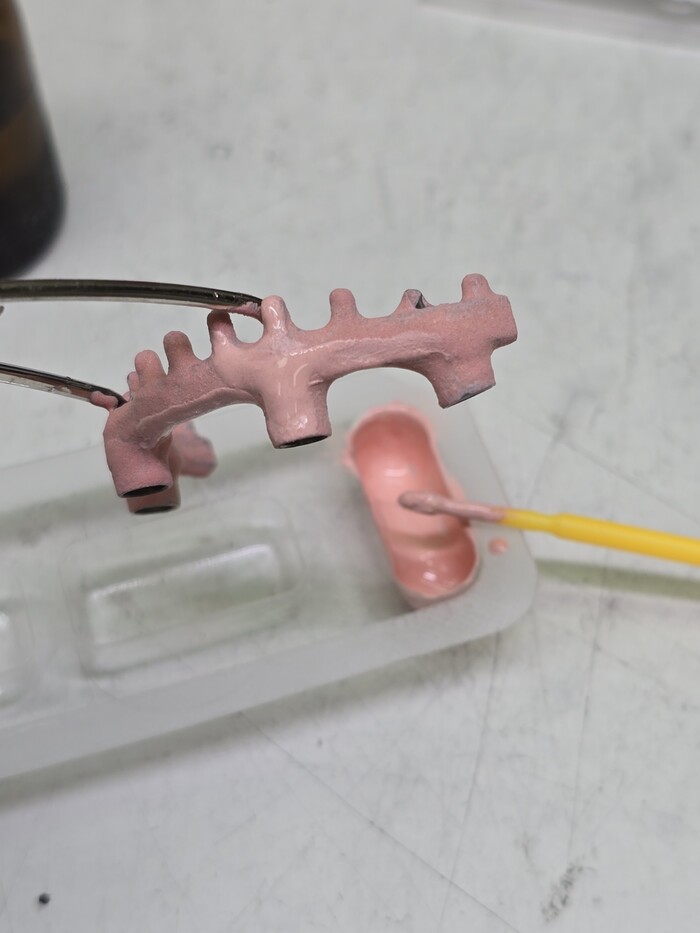

Полимер (порошок) и мономер (жидкость) взвешиваю на весах, получается жидкая смесь для заливки в формы. Процесс полимеризации (затвердевания) пластмассы протекает в воде и под давлением 2.5 атмосферы.

Спустя 30 минут протезы готовы к обработке.

верхний протез – временный, по этому у него изначально смоделирована десна. Нижний – постоянный. На него буду наносить фотополимерный композит, схожий или такой-же как и пломбировочный материал.

Надо спилить литники, обработать края, пространство между зубов.